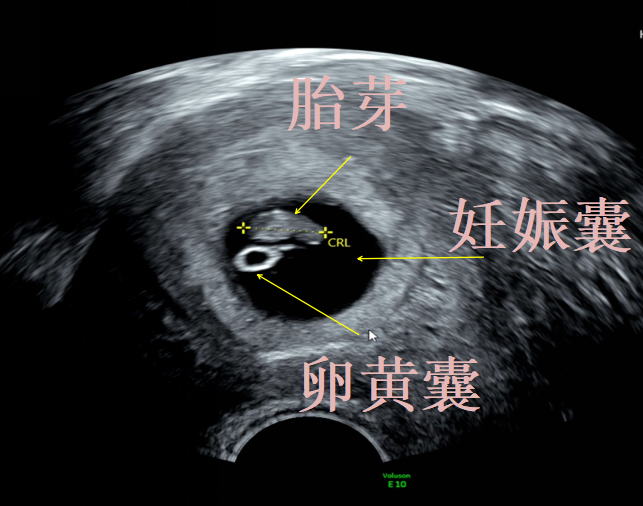

在考虑调药前,必须进行一轮“侦探式”排查。这是所有后续治疗的根本依据。首要检查是B超,也是最关键的一步。需要确认胚胎是否存活?胎心是否良好?是否存在绒毛膜下血肿(宫腔内出血区域)胚胎发育大小是否符合孕周?